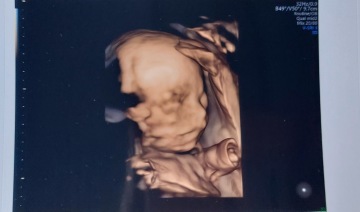

Jmenuji se Petra a jsem maminka samoživitelka šestileté dcerky. Společně žijeme ve skromném bytě 1+1. Momentálně jsem v pátém měsíci těhotenství, ale místo radostného očekávání zažívám obrovský stres. Z důvodu zpožděné výplaty superdávky jsme odkázány na příjem 9 345 Kč měsíčně.

K běžným výdajům se mi nyní přidávají i náklady spojené s těhotenstvím. Musím dojíždět na specializovaná vyšetření a z vlastního doplácet na nezbytné screeningy.